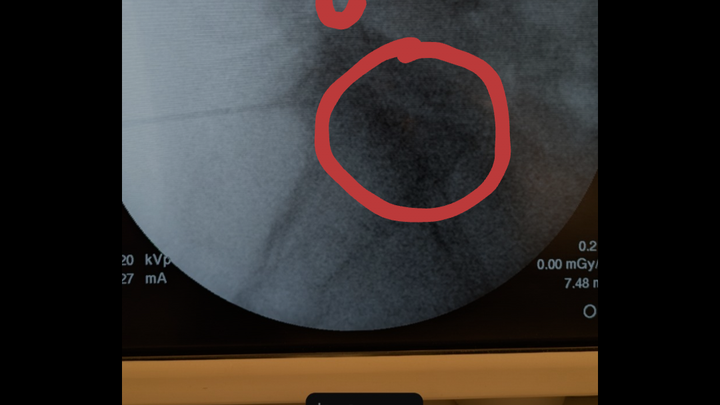

Hello, my name is Carmina Mora. I have been dealing with ongoing back and other medical issues, which have not only caused me significant discomfort and pain but have also resulted in financial hardship due to the amount of time I had to take off work.

I was advised over a year ago that I needed back surgery, but due to financial constraints, I was unable to proceed with it at the time. Unfortunately, my condition has since worsened to the point where surgery is now essential, and I had scheduled the procedure for April 4.